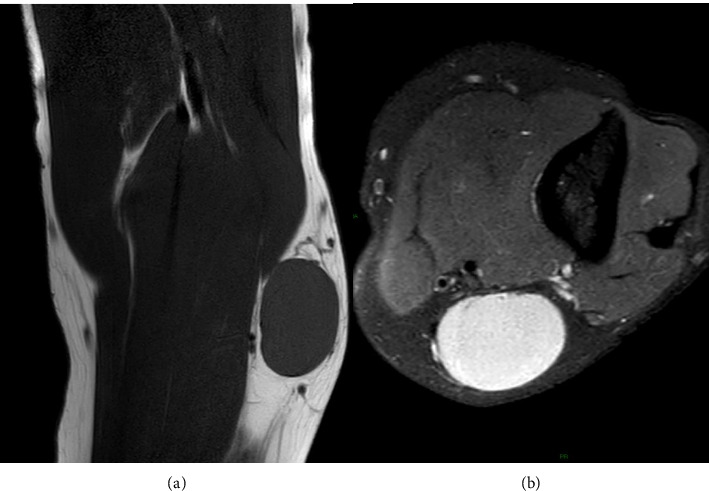

Hodgkin lymphoma (HL) is a type of lymphoma, characterized by the presence of abnormal Reed-Sternberg cells. It typically affects lymph nodes, generally in the upper body (such as neck, chest, and armpits). It can also involve the spleen, liver, and bone marrow. In the literature, there are sporadic cases of atypical localization of HL. The aim of this article is to report a peculiar case of HL in a 55-year-old male presenting with primary epitrochlear lymphadenopathy as the only localization of disease, also performing a literature review on this atypical presentation. We also summarized the possible underlying malignant pathologies that arise from the soft tissues of the upper limb adjacent to the elbow.